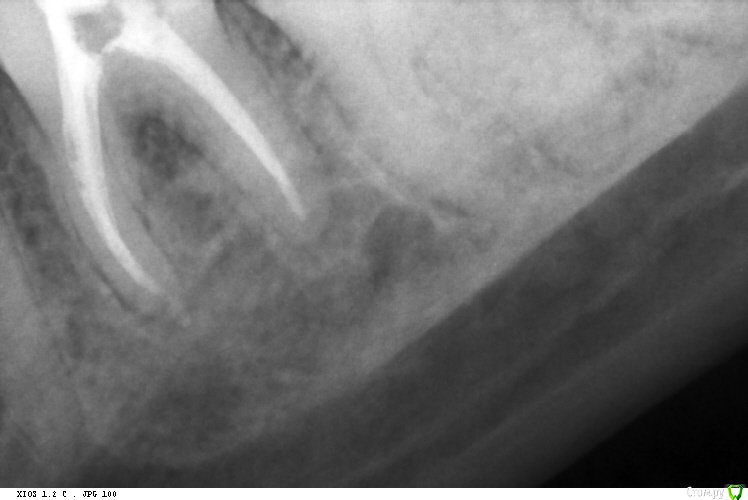

St. Опубликовано 29 октября, 2016 Автор Поделиться Опубликовано 29 октября, 2016 Реколл случая http://forum.stom.ru/topic/29857-endo/?p=529024. Прошло 11 месяцев после пломбировки)) 3 Ссылка на комментарий

Fred Опубликовано 29 октября, 2016 Поделиться Опубликовано 29 октября, 2016 Реколл случая http://forum.stom.ru/topic/29857-endo/?p=529024. Прошло 11 месяцев после пломбировки)) А почему такие жесточенные поры под реставрацией? Ссылка на комментарий

vse32 Опубликовано 29 октября, 2016 Поделиться Опубликовано 29 октября, 2016 А почему такие жесточенные поры под реставрацией? Может устья чем заливали, не контрастным. Свет, СИЦ? Ссылка на комментарий

St. Опубликовано 29 октября, 2016 Автор Поделиться Опубликовано 29 октября, 2016 (изменено) А почему такие жесточенные поры под реставрацией?Текучка градии нерентгенконтрастна. Как и сам материал большинства цветов. Керамика в планах. Ждали динамики. Изменено 29 октября, 2016 пользователем St. Ссылка на комментарий